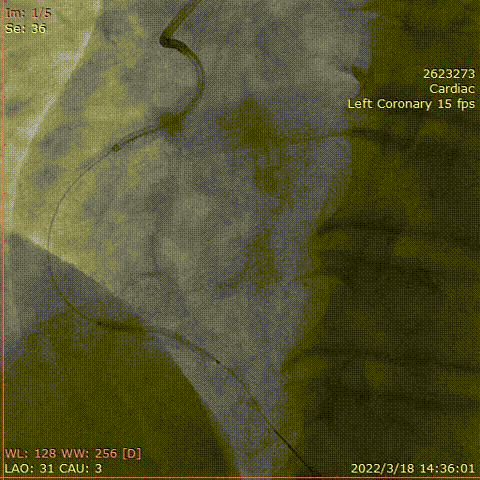

对右冠脉行介入治疗,钙化较重

考虑指引导管支撑不佳,病变钙化重,血管迂曲,Telescope™导引延长导管支撑下,远段选择药物球囊PTCA

中断至近段置入支架